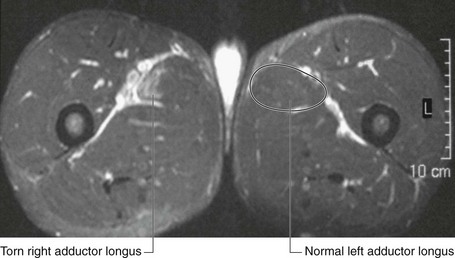

In the clinic Muscle injuries and strains

Muscle injuries and strains tend to occur in specific muscle groups and usually are related to a sudden exertion and muscle disruption. They typically occur in athletes.

Muscle tears may involve a small interstitial injury up to a complete muscle disruption (Fig. 1.27). It is important to identify which muscle groups are affected and the extent of the tear to facilitate treatment and obtain a prognosis, which will determine the length of rehabilitation necessary to return to normal activity.

image

Fig. 1.27 Axial inversion recovery series, which suppresses fat and soft tissue and leaves high signal intensity where fluid is seen. A muscle tear in the right adductor longus with edema in and around the muscle is shown.